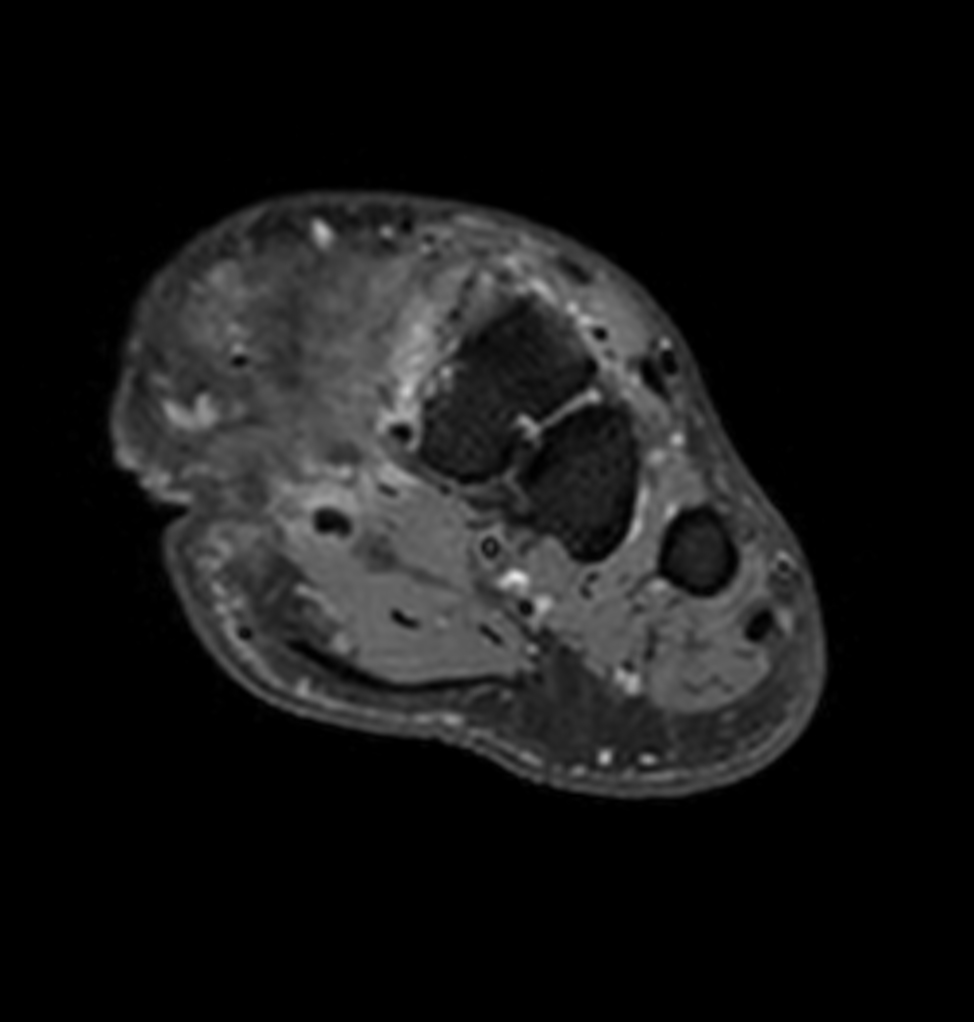

Ankle/Foot imaging post-amputation

Patient with partial amputation of the foot

Axial T1w mDIXON XD TSE with gado (Water only)

Axial T1w mDIXON XD TSE with gado (In Phase)